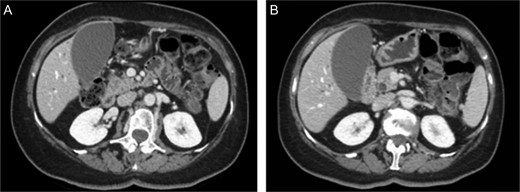

First the abdominal ultra sonography (AUS) and then CT scan revealed the presence of well-defined hypodense pancreatic head mass of 2 cm of diameter, determining bile duct and Wirsung’s duct dilatation; mesenteric vessels were clearly free of infiltration, no liver or lung suspected lesions were detected as well as volume increased lymph nodes (Fig. 1). Ecoendoscopic ultra sonography (EUS) confirmed the presence of a hypoechoic and well-defined pancreatic head mass (18 × 15 mm) and without sign of vessels infiltration (Fig. 2). A fine-needle aspiration (FNA) was performed and histopathological examination showed the presence of neoplastic cells with morphological features like the lung ones and consistent with metastasis from primary adamantinoma.

EUS. EUS confirmed the presence of a hypoechoic and well-defined mass of diameter 18 × 15 mm.